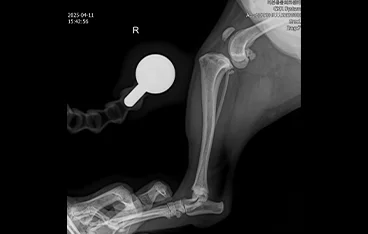

• THR

• THR 전

THR 후